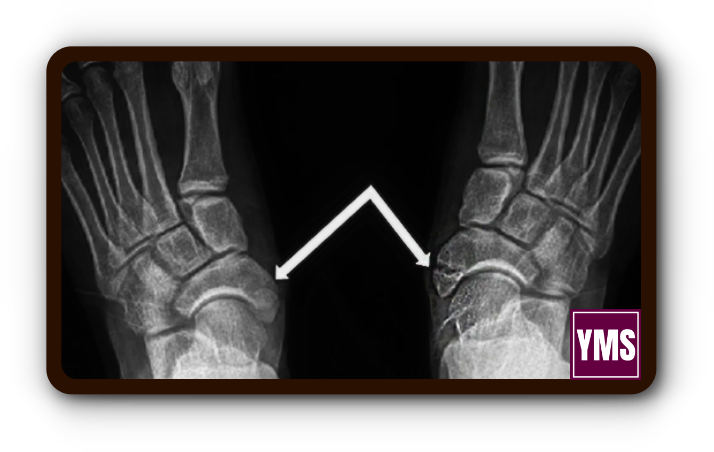

질병의 진단 방법

부주상골 문제를 진단하는 방법은 크게 두 가지입니다. 첫 번째는 방사선 촬영으로, 이를 통해 부주상골과 주상골 사이의 상태를 확인할 수 있습니다. 두 번째는 CT나 MRI 검사로, 이를 통해 후경골건의 퇴행성 변화를 확인할 수 있습니다.